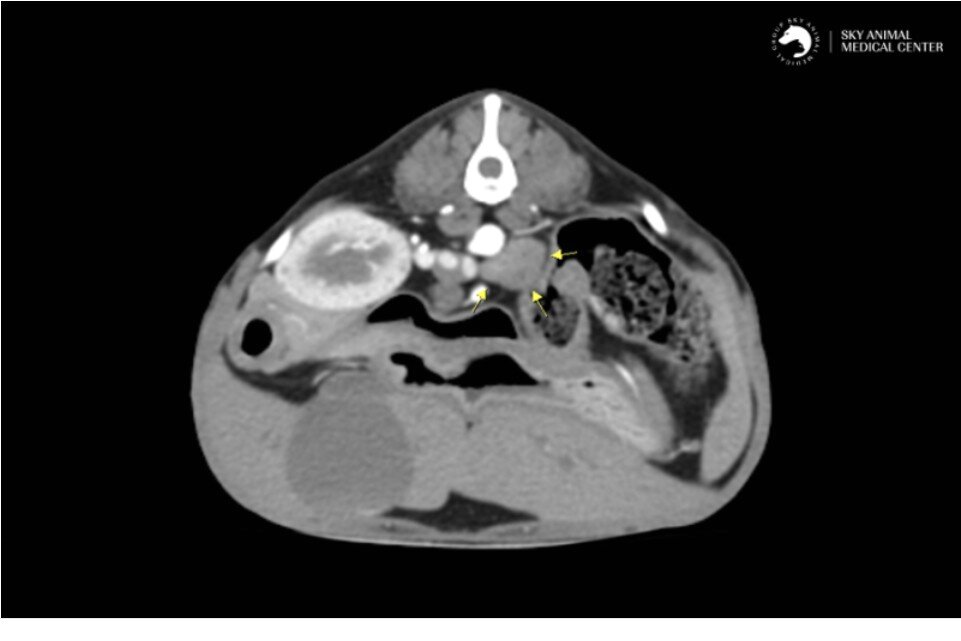

본문 이미지 - 쫑이의 CT 검사 결과 좌측 부신에 비정상적으로 커진 종양이 발견됐다(스카이동물메디컬센터 제공). ⓒ 뉴스1

쫑이의 CT 검사 결과 좌측 부신에 비정상적으로 커진 종양이 발견됐다(스카이동물메디컬센터 제공). ⓒ 뉴스1